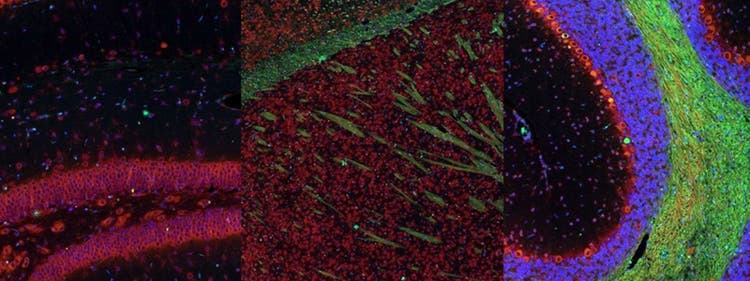

Fluorescence imaging of a mouse brain

これらの画像は一つひとつが独立した拡大画像に見えますが、すべて合わせると、蛍光イメージングで撮影されたマウスの脳の画像が形作られます。

イギリスの科学者、George G. Stokes卿は、蛍石に紫外線を当てると蛍光を発することを最初に発見し、「蛍光」という用語を作りました。Stokes卿は、蛍光は励起光よりも波長が長いことに気づき、今日では、この現象はストークスシフトとして知られています。蛍光顕微鏡法は、自然のまま(一次蛍光または自家蛍光と呼ばれます)か、蛍光を発することのできる化学物質で処理した場合(二次蛍光として知られています)かのいずれかで蛍光を発することのできる物質を研究するための優れた方法です。